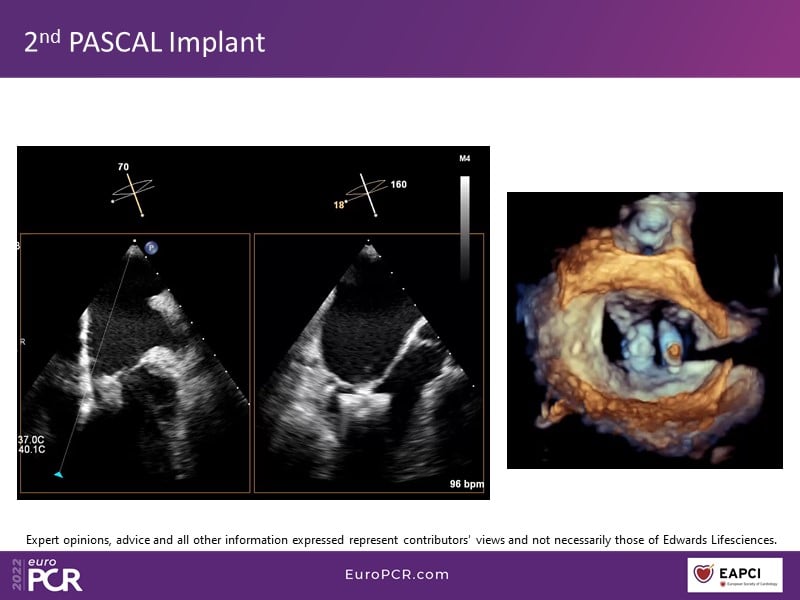

With study outcomes and clinical cases, this EuroPCR 2022 session will enable you to discuss the anatomical considerations that define suitable candidates for treatment of mitral regurgitation with the PASCAL platform and highlight key differentiators and tips and tricks for its use.

- To discuss which anatomical considerations define suitable candidates for the treatment of mitral regurgitation with the PASCAL platform

- To attend case-based discussions that will highlight key differentiators and tips and tricks when using the PASCAL platform to treat mitral regurgitation

- To participate in a recorded case demonstration using the PASCAL platform for the treatment of mitral regurgitation